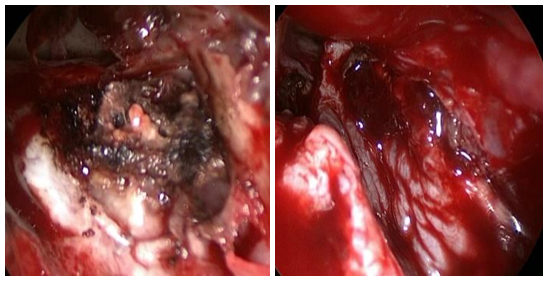

Figures 3A-C Lateral Sphenoid wall MC, multilayer closure technique.

Intranasal MC was the most frequent lesion (6/5) and there was one patient with MEC (1/6). Five cases were idiopathic and one patient had history of transnasal surgery for a tumor of the sellar region and sphenoid plane 15 days before. 83,3% of the cases were primary surgeries and one patient had 3 prior MC surgeries. In 2 cases the MC was located in the sphenoid lateral wall (Figures 1A-B), one was located in the sphenoid roof (Figure 2), 2 in the cribriform plate and one patient, with MEC diagnosis, had it located in the frontal sinus. 66,6% had anterior rhinorrhoea (4/6) (Table 1). All patients were studied before surgery, only in four of them (66,6%) the lesion location was detected by at least one of the studies (CT, MRI and/or endoscopy). For one patient with MC of the lateral sphenoid wall intrathecal fluorescein was used prior to surgery (10cc of CSF were extracted by lumbar puncture and mixed with 0.2ml of 5% fluorescein, then 1ml per minute was delivered by intrathecal injection. We performed a multilayer closure technique in all patients (Figures 3A-C). In 4 cases we used autologous fat with mucoperichondrium (Figures 4A-B) and (Figures 5A-C) and in 2 cases autologous cartilage with mucoperichondrium. We used an intranasal transpterygoid approach for one case of lateral sphenoid wall mucocele, a Draf III technique in une case of frontal sinus MEC (Figures 6A-E). During the immediate postoperative period, one patient had acute meningitis that resolved with intravenous empirical antibiotics. One patient had a CSF leak recurrence 4 months after surgery. He was treated by external approach and had no relapse. No complications during postoperative follow up. The success rate of the reconstructions performed by endonasal approach was 83.33% (5/6). The average follow-up of the patients was 15 months.